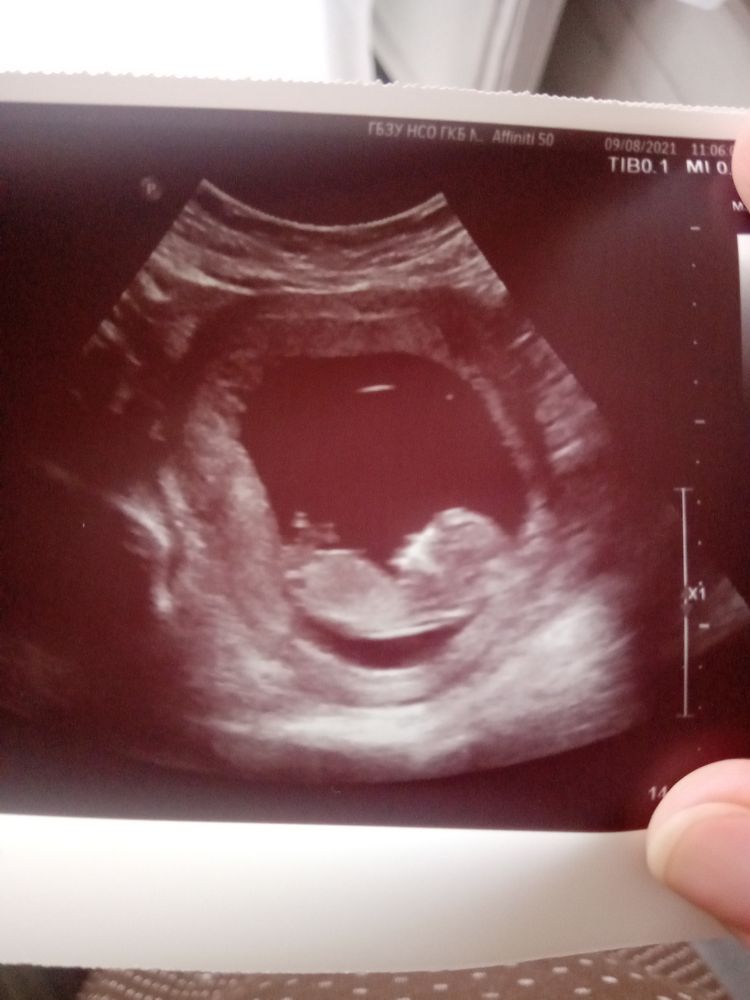

Первый скрининг 😍

Какой хороший пост👍 Милое фото, прям мужчина в профиль, ни дать, ни взять!!🙈

Lucy, да-да, носатенький, видимо, будет. Папа наш обладатель нескромного носика)))))

Мальчишка лежит, Юль 😉☺️ Здоровья, Легкой беременности, пусть всё будет хорошо 😘